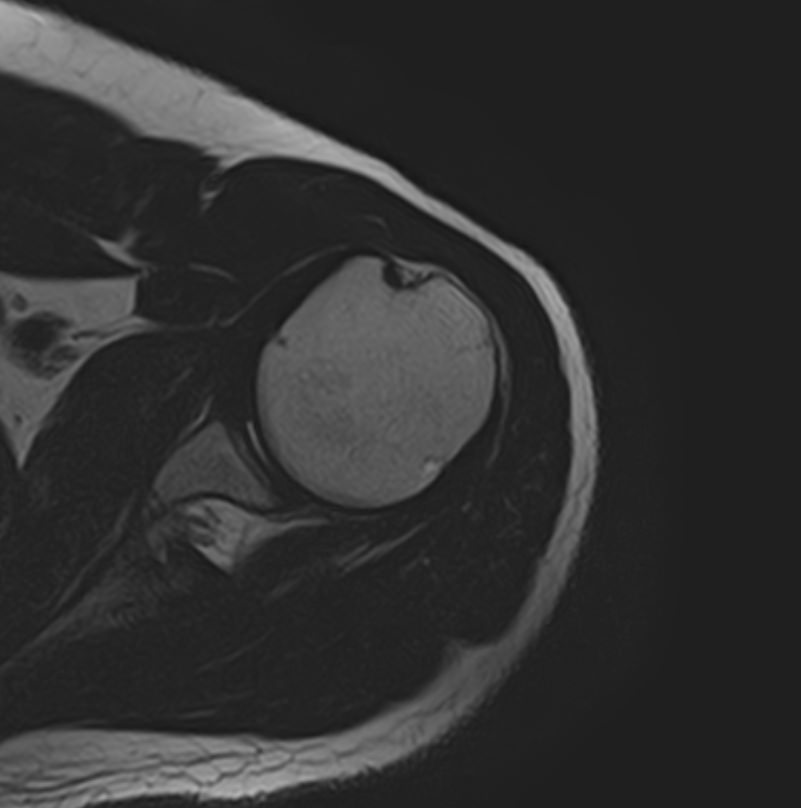

Для того, чтобы оценить состояние шейных позвонков с прилегающими тканями и одновременно визуализировать плечевой сустав, в нашей клинике выполняется комплексное обследование, включающее два протокола: МРТ шейного отдела позвоночника и МРТ плечевого сустава.

Метод МРТ позволяет оценить состояние всех анатомических областей шейного отдела позвоночника: костную структуру позвонков, спинной мозг с отходящими от него нервными корешками и окружающие мягкие ткани. Протокол обследования плечевого сустава включает оценку костной структуры, суставной капсулы, полости сустава с выстилающей его синовиальной оболочкой, связок, сухожилий, мышц и окружающих мягких тканей.